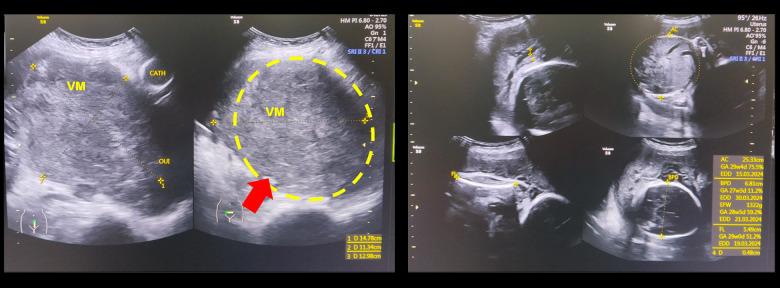

背景 孕期外阴黑色素瘤极为罕见。孕期的激素和免疫变化引发了人们对黑色素瘤进展加速及孕产妇预后较差可能性的担忧。本病例报告描述了一名孕妇外阴黑色素瘤的不寻常表现,尽管此前接受过治疗,但病情仍迅速进展,不过胎儿结局良好。病例报告 一名40岁、孕3产2、流产0次的女性,孕28周,有3年前诊断为外阴恶性黑色素瘤的病史,出现突发腹痛和血尿。她此前接受过6个疗程的化疗。体格检查发现右侧外阴有一个3厘米的肿块,而超声检查在宫颈发现一个高回声实性肿块,乳酸脱氢酶水平升高。鉴于疾病已进展,医疗团队进行了剖宫产子宫切除术、因子宫体受累行阴道切开术以及因医源性撕裂伤进行膀胱修复。组织病理学检查结果证实宫颈和子宫体有转移性外阴黑色素瘤。由于IV级黑色素瘤进展,妊娠在27周时终止,但新生儿出生时情况稳定。不幸的是,患者术后1个月死亡。结论 本病例强调了孕期黑色素瘤侵袭性进展的可能性,可能因生理变化而加剧,但也突出了胎儿的良好结局。虽然化疗可能会对外生殖系统产生不利影响并可能导致不孕,但该患者能够受孕,本病例说明了妊娠与癌症进展之间复杂的相互作用。